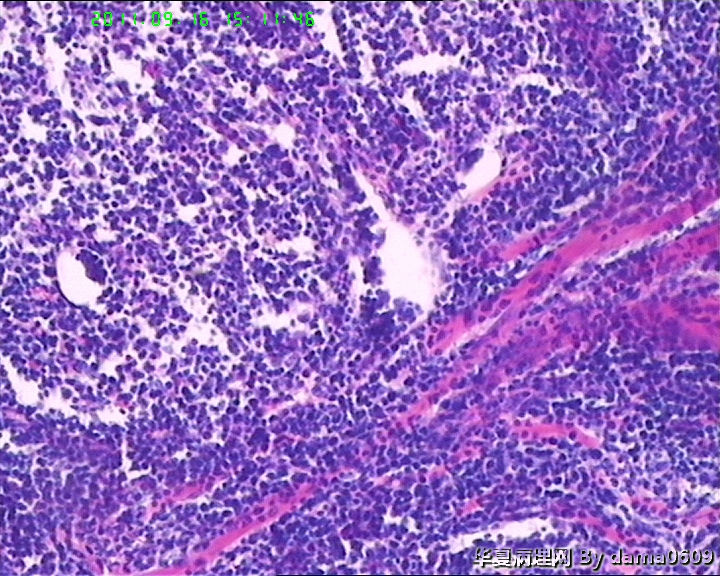

• 背部肿物,急请老师看看!!图2

图2